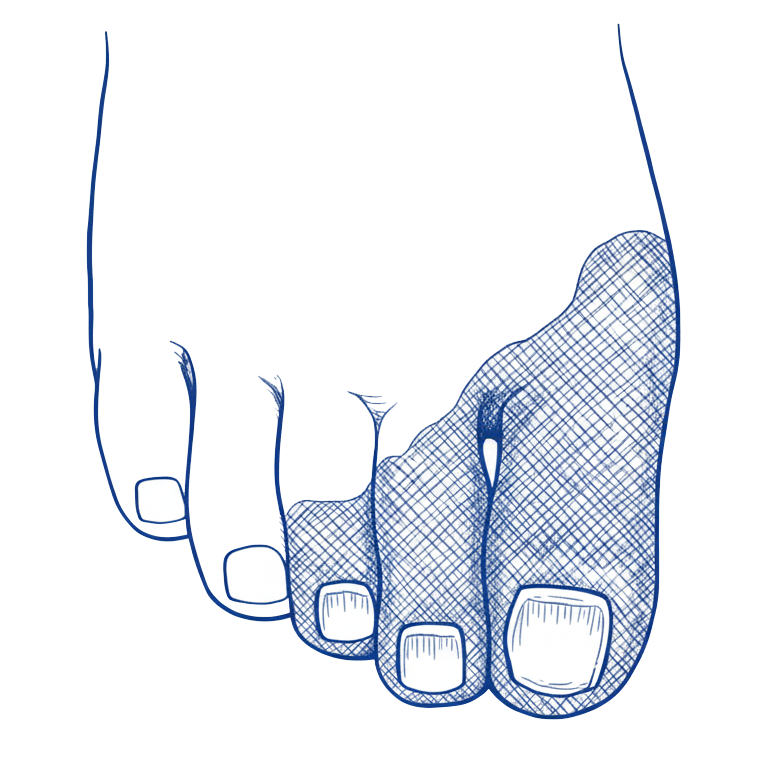

Diabetiese Voetulkusse

Wonde van die voete, voetsole en onderbene van pasiënte met diabetes. Hierdie wonde mag ontstaan weens ingekorte sensasie (neuropatie) of ingekorte arteriële toevoer (ischemie) of ’n kombinasie van bogenoemde (neuro-ischemie)